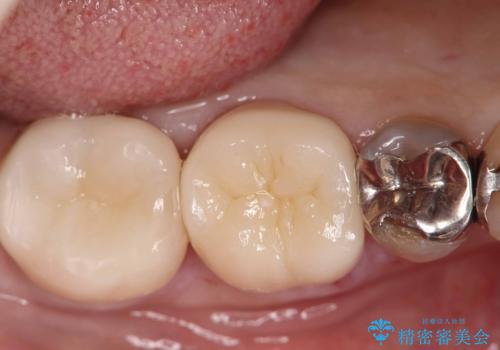

銀歯の下の虫歯|オールセラミッククラウン

担当医 河野豊嘉